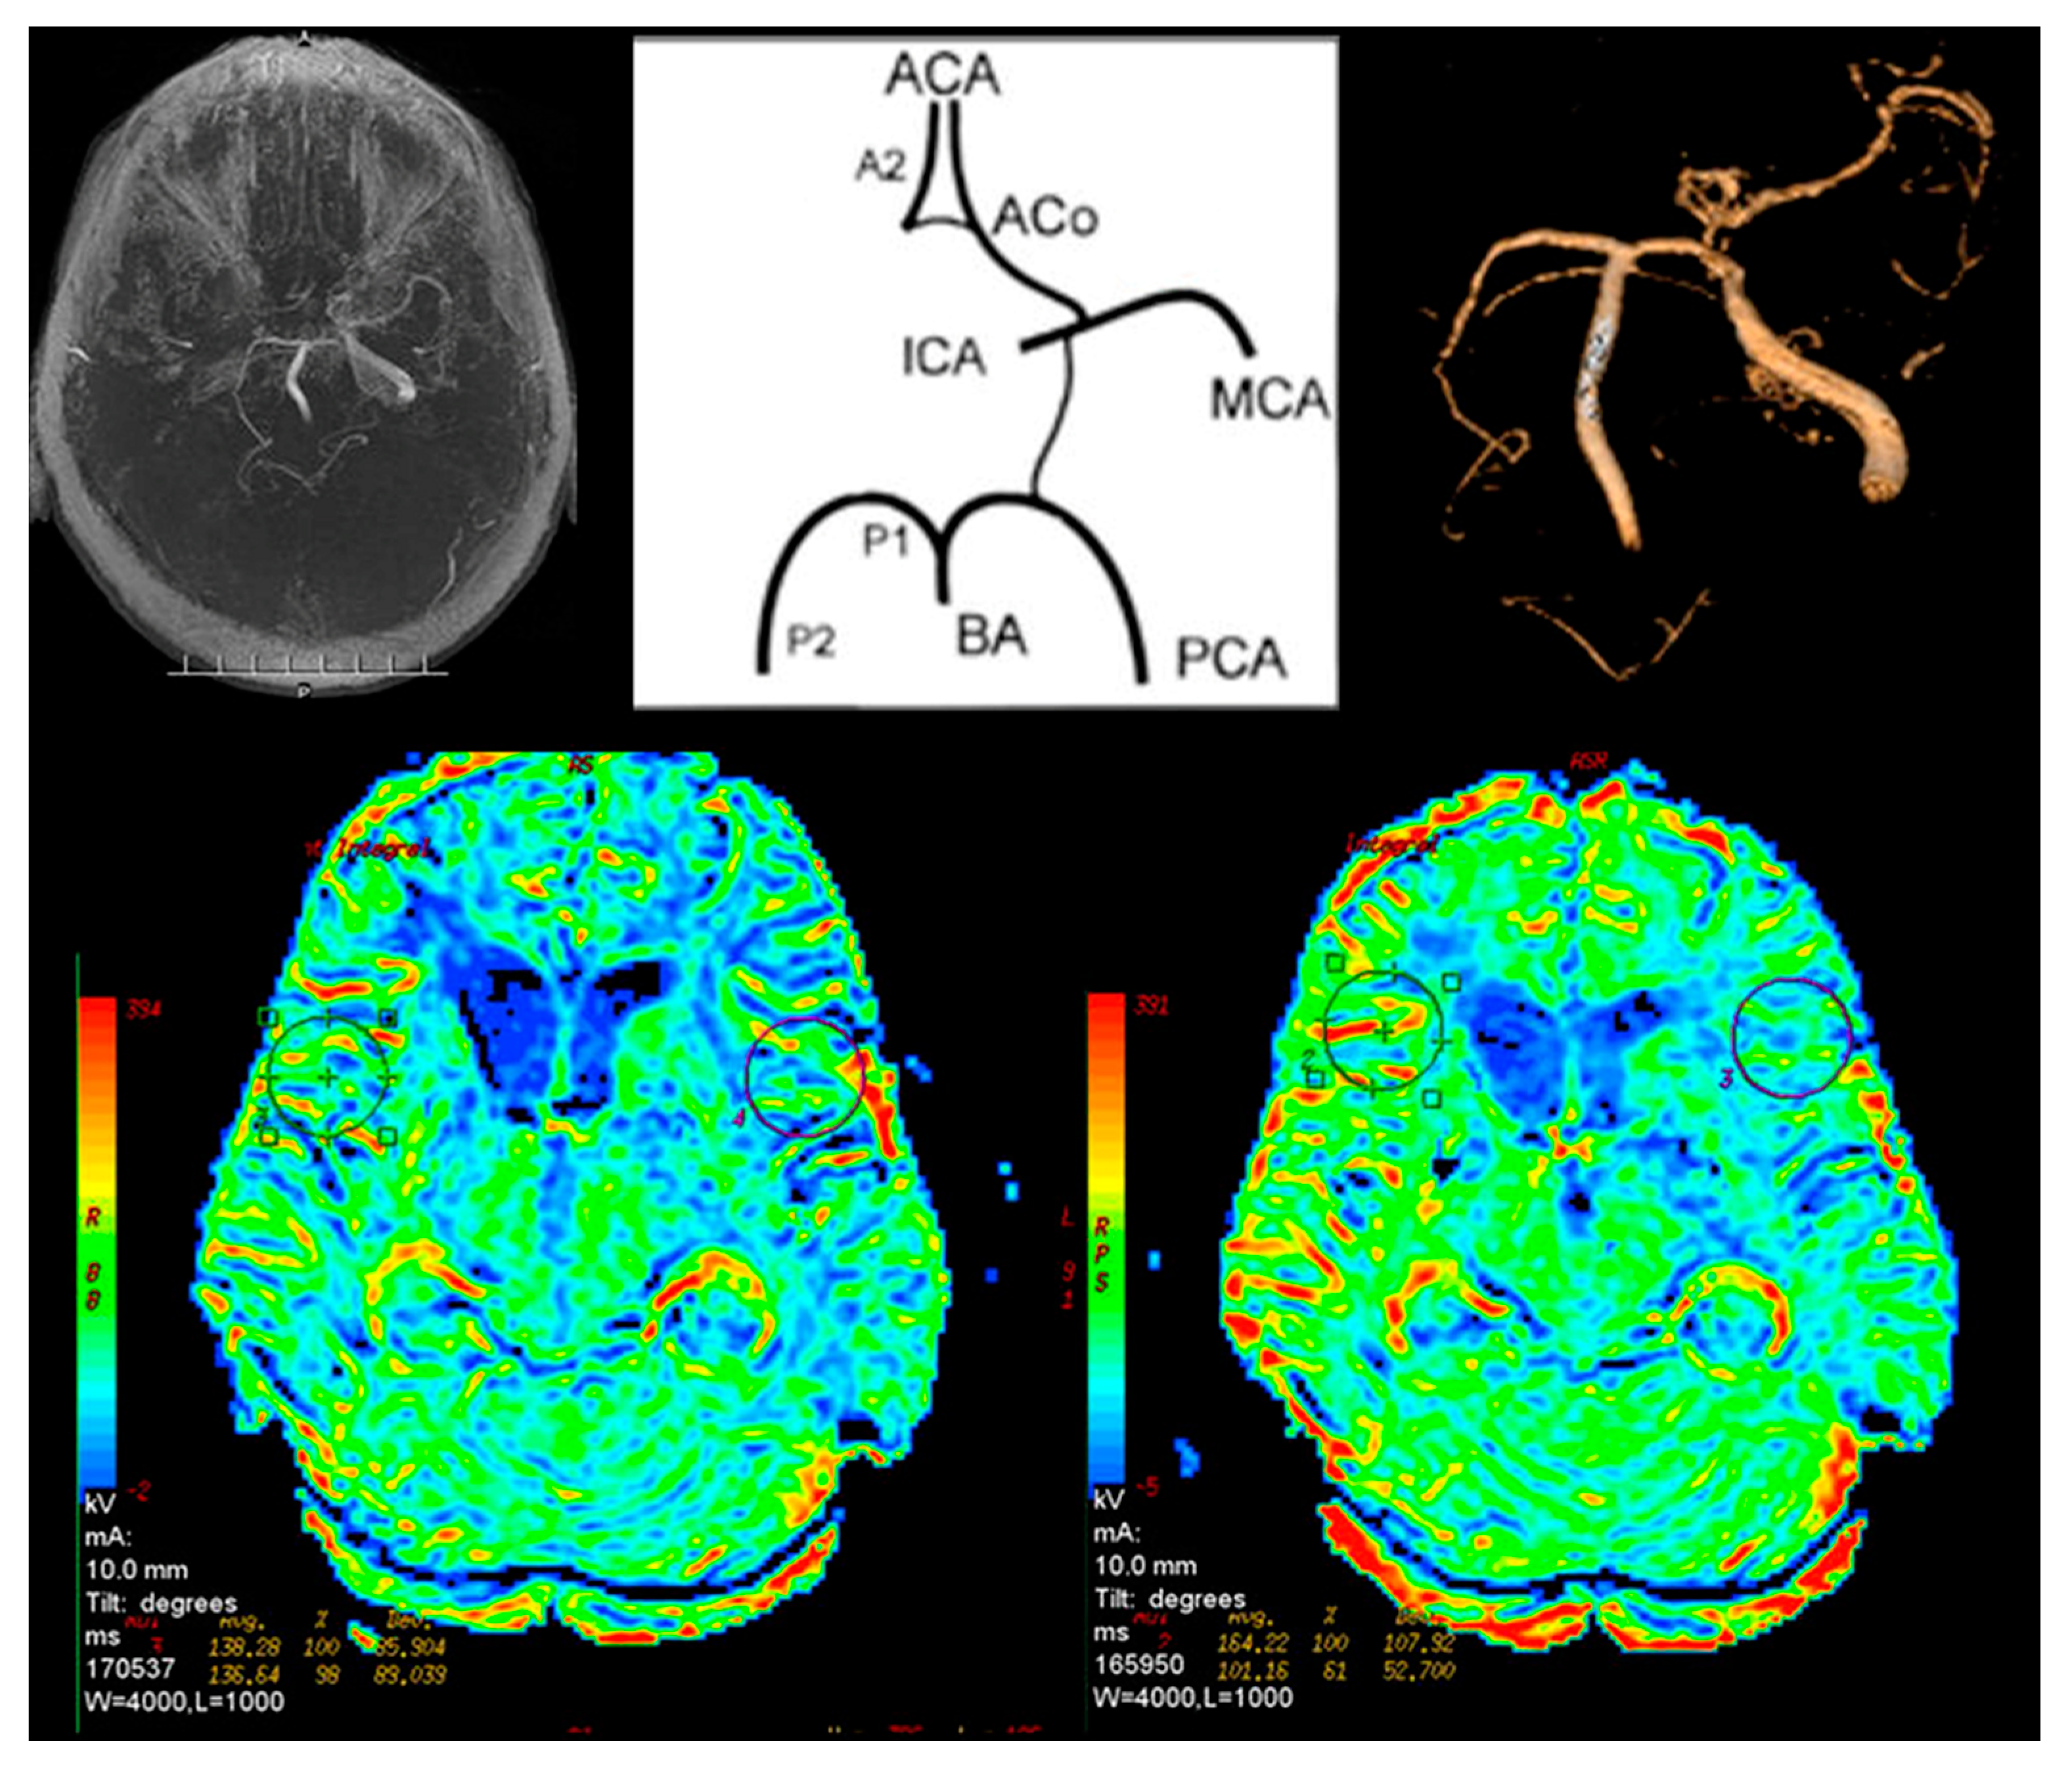

The circle of Willis had a normal anatomy in three patients from Group I (7.5%) and in eight from Group II (53%). Other patients from both groups had single or multiple abnormalities (Figure 3).

The only pathology found in Group II was bilateral (three patients) or unilateral (five patients) lack of posterior communicating artery (PCoA). In Group I the first segment of the anterior cerebral artery (A1) was absent in 21 patients (52.5%). Twelve patients (30%) had decreased A1 signal. In 12 cases (30%) the anterior communicating artery (ACoA) was absent (Table 2). In 29 cases (72.5%) no flow in the PCoA was observed. One patient had no signal in the first segment of the posterior cerebral artery (P1). Among five patients from Group I, carotisation was observed.

In Group I, 24 patients (60%) had abnormalities in cerebral perfusion parameters on P-MR without Acetazolamide. In 15 patients there was a reduction in perfusion in the hemisphere on the affected side. In PA-MR, perfusion disorders were found in all subjects. In 28 cases, they appeared on the affected side (Figure 4).

In Group II in one patient (6.6%), after the basic P-MR, perfusion disorders on the operated side were observed. In six cases (40%) with PA-MR the differences between the hemispheres were greater than 10%. They corresponded to the operated side.

Figure 3. Magnetic resonance brain perfusion with Acetazolamide and magnetic resonance angiography of the intracranial arteries. Right internal carotid artery—100%, left internal carotid artery—70%. Differences after admission of Acetazolamide marked with circles (right side).